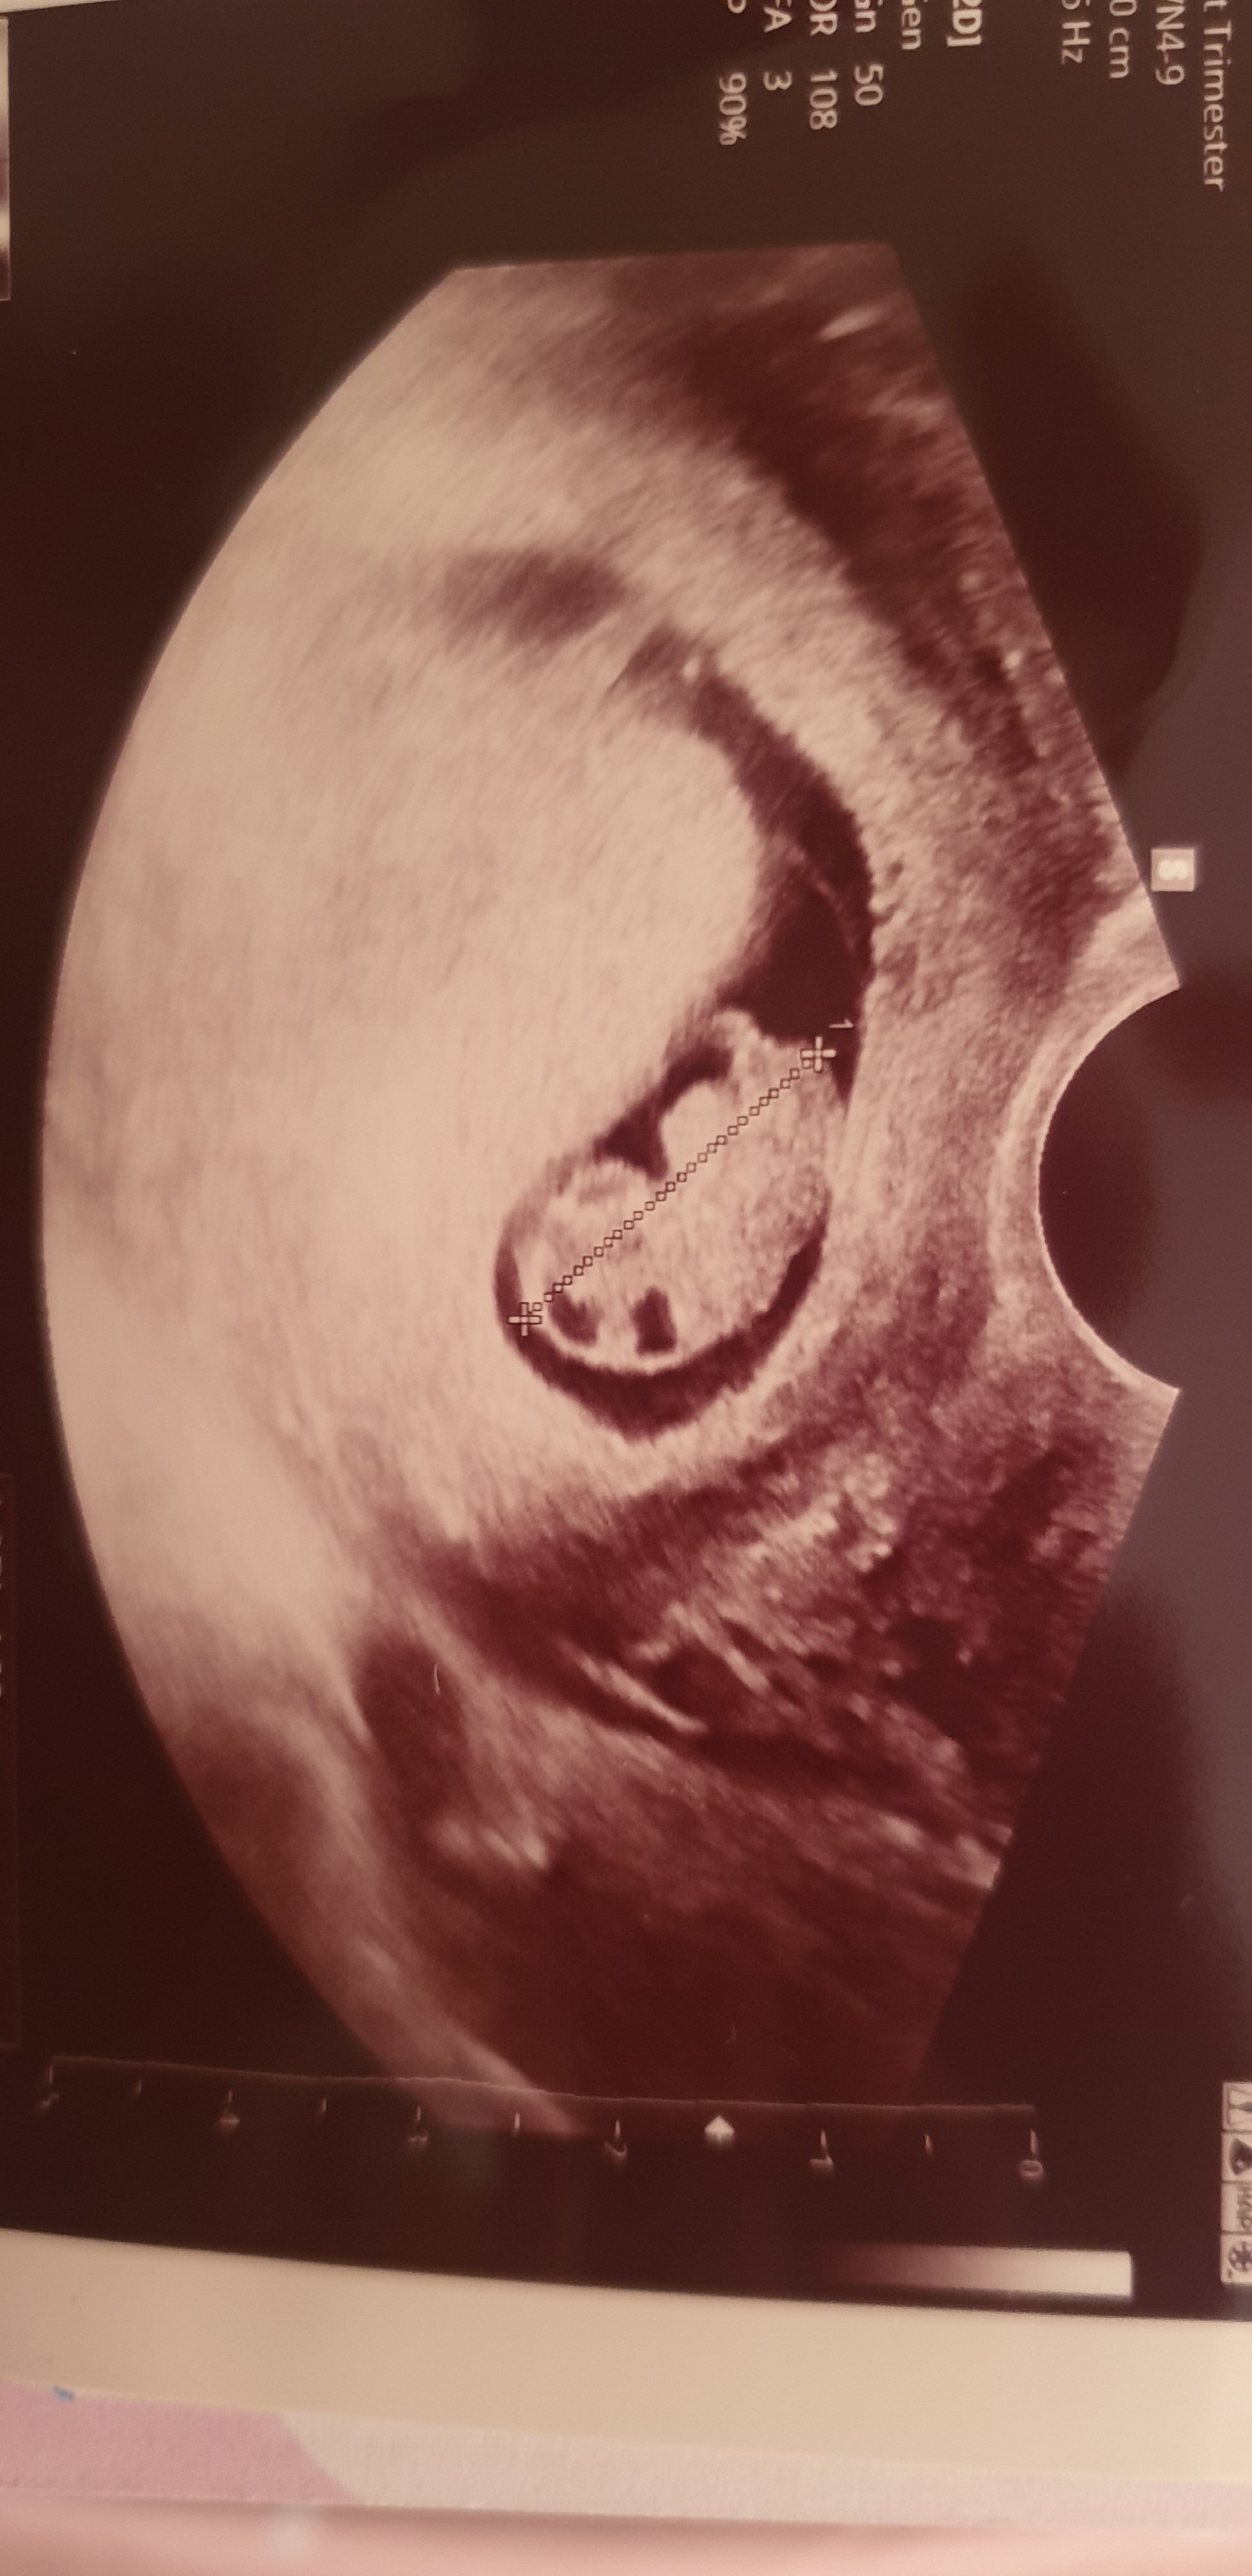

Jestem po wizycie, lekarz stwierdził że tak ruchliwego maluszka dawno nie widział bo nie mógł dokładnie zmierzyć ale coś koło 2cm. Rączkami rusza pięknie. Serducho też bije idealnie. To co u mnie się zmieniło to wiek ciąży, jest o kilka dni młodsza i termin jednak na 20.11 czyli na moje urodziny :)

Mój lekarz do którego chodzę prywatnie i mam pełne zaufanie, stwierdził że pappa warto zrobić i kosztuje 75zl a prenatalne to koszt 50zl wiekszy niz normalne usg czyli 230zl wiec do tego co z luxmed byłam zapisana to nie ide. Prenatalne 11maja mam. oooo wstawiam Wam fotkę :)

@Ana 17.2020 super wieści :-) Cudne zdjecie.. Ktory to tydz?